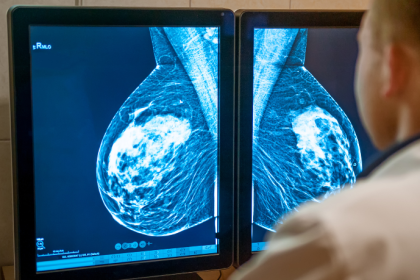

Cuando la mamografía muestra alteraciones benignas: Entienda con Vinicius Tadeu Sattin Rodrigues

Recibir un informe con alguna alteración en la mamografía suele generar una…